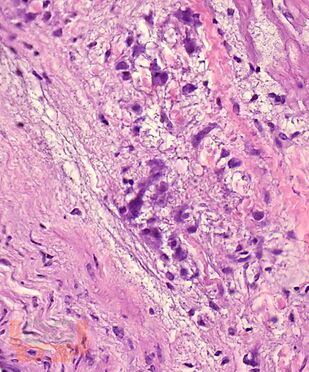

В учебном пособии представлен теоретический материал, перечень макропрепаратов и микропрепаратов, демонстрирующих типовые проявления патологических процессов. В цветных иллюстрациях и в описании микропрепаратов cделан акцент на наиболее важных гистологических изменениях, позволяющих на светооптическом уровне диагностировать и дифференцировать состояния, отклоняющиеся от нормы, в том числе с использованием различных гистологических окрасок. Пособие помогает выделить главные аспекты изучаемых патологических процессов, организовать и конкретизировать учебный процесс.